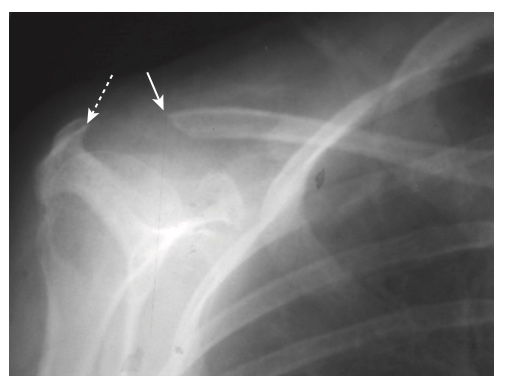

- Ăn mòn đầu xa xương đòn (Hình -3)